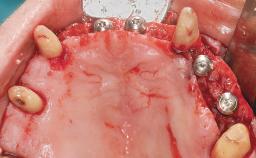

A 35-year-old Caucasian female presenting with advanced periodontal disease involving both the maxillary and the mandibular dentition was referred for evaluation. The patient, a non-smoker in good general health, requested treatment for recurrent periodontal abscesses, tooth mobility, and discomfort during chewing, as well as restoration of her missing teeth with a fixed prosthesis to improve mastication and esthetics. All residual maxillary teeth exhibited plaque deposits, deep pockets, bleeding on probing, and class III mobility and were evaluated as hopeless. All residual mandibular teeth except tooth 37 could be maintained after periodontal therapy.

| Bone Augmentation | Horizontal|Staged|Vertical |

| Augmentation Materials | Autogenous block(s) |

| Soft Tissue Grafting | Staged |